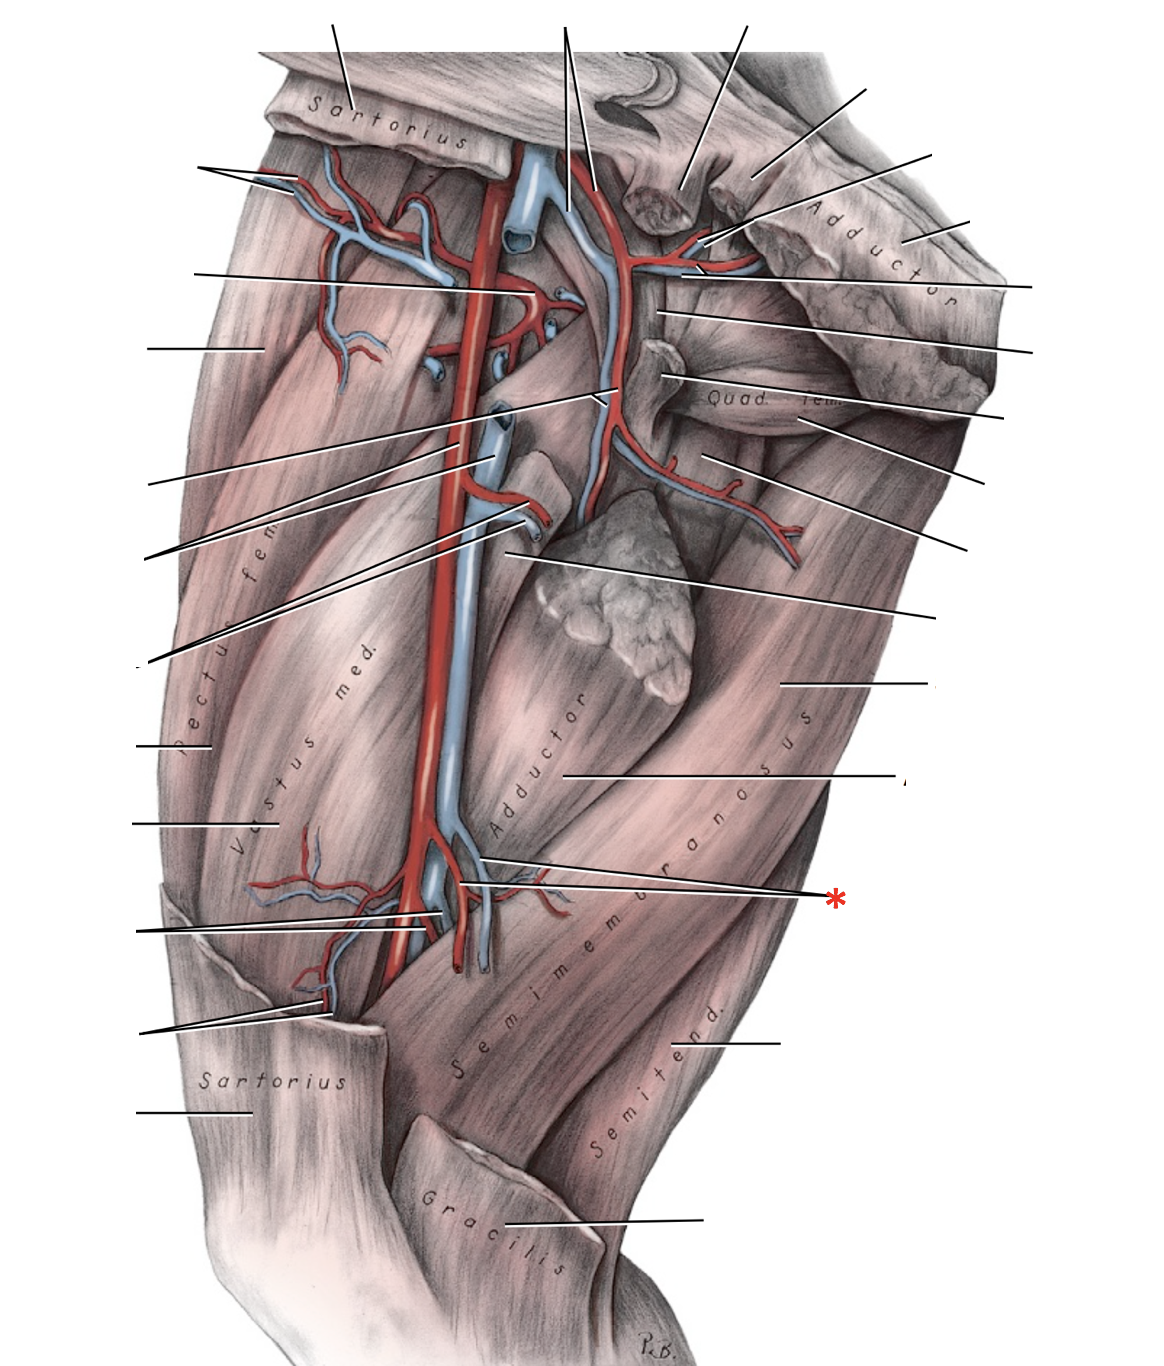

M. popliteus

Origin: Fossa m. poplitei of femur

Insertion: Linea m. poplitea (Proximal Tibia)

Action: Flex stifle, rotate leg medially

Innervation: N. tibialis

Blood supply: A. poplitea

M. popliteus

Origin: Fossa m. poplitei of femur

Insertion: Linea m. poplitea (Proximal Tibia)

Action: Flex stifle, rotate leg medially

Innervation: N. tibialis

Blood supply: A. poplitea

N. tibialis

A. saphena r. caudalis

A. saphena

A. saphena